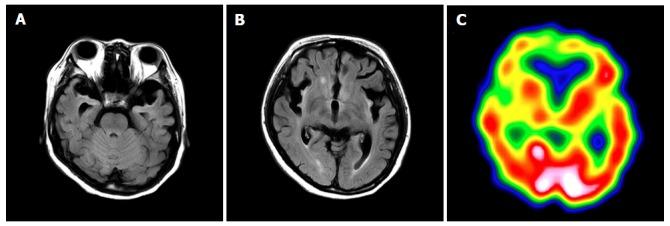

一名患有鸟氨酸转氨甲酰酶缺乏症的女性患者产后发生高氨血症危象。

Hyperammonemia crisis following parturition in a female patient with ornithine transcarbamylase deficiency.

Ornithine transcarbamylase deficiency (OTCD) is an X-linked disorder, with an estimated prevalence of 1 per 80000 live births. Female patients with OTCD develop metabolic crises that are easily provoked by non-predictable common disorders, such as genetic (private mutations and lyonization) and external factors; however, the outcomes of these conditions may differ. We resuscitated a female patient with OTCD from hyperammonemic crisis after she gave birth. Hyperammonemia after parturition in a female patient with OTCD can be fatal, and this type of hyperammonemia persists for an extended period of time. Here, we describe the cause and treatment of hyperammonemia in a female patient with OTCD after parturition. Once hyperammonemia crisis occurs after giving birth, it is difficult to improve the metabolic state. Therefore, it is important to perform an early intervention before hyperammonemia occurs in patients with OTCD or in carriers after parturition.

摘要

Clinical and cranial MRI features of female patients with ornithine transcarbamylase deficiency: Two case reports.鸟氨酸转氨甲酰酶缺乏症女性患者的临床及头颅MRI特征:两例报告

Medicine (Baltimore). 2019 Aug;98(33):e16827. doi: 10.1097/MD.0000000000016827.